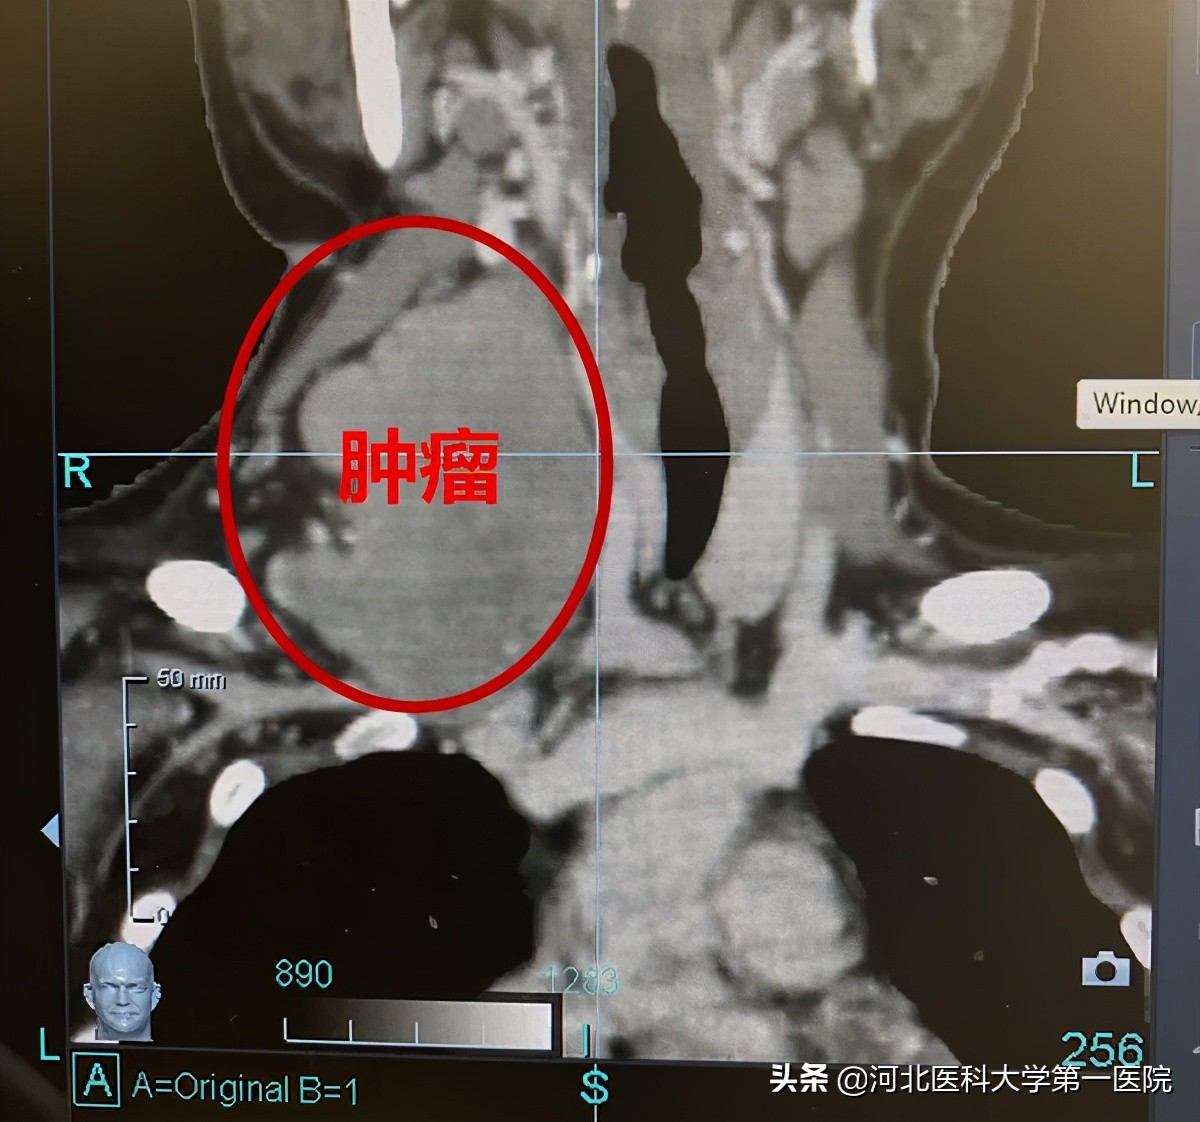

肿瘤大小

9.6cm*4.4cm*8.6cm

21岁小花正是未来可期的年纪,却在3个月前发现脖子右侧的包大了不少,而且包块随着时间推移越来越大,于是小王便到当地医院检查,查CT肿物大小如芒果一般大小,为9.6cm*4.4cm*8.6cm,穿刺取病理为梭形细胞肿瘤,考虑为纤维瘤病。晴天霹雳的噩耗,一家人立即前往北京看病,经多学科会诊认为,肿瘤侵犯范围大,手术存在较大的风险,建议保守治疗。

可是,这个肿瘤大到已经侵犯到前中后斜角肌、肩胛提肌,臂丛神经压迫的她,右侧胳膊都已经无法抬起来,严重影响日常生活。如果肿瘤不切除就会发生肿瘤压迫气管导致窒息,而且病理显示该肿瘤介于良性和恶性之间,但手术就会无法避免的损伤的神经,即便是摘除了肿瘤,也会造成无法挽回的损伤。